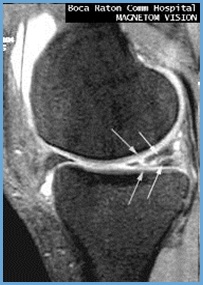

Der krankenhausaufenthalt dauert selten länger als eine woche. Ein anriss des innenmeniskus zählt zu den häufigsten sportverletzungen überhaupt. Bei einer solchen verletzung genügt in der regel eine sportpause von etwa drei wochen. Zu einem meniskusriss führen können. Er sieht aus, als würde sich ein henkel am meniskus bilden und erstreckt sich vom vorderen (vorderhorn) bis zum hinteren anteil. Je nachdem, welche teile der knorpelscheibe betroffen sind, werden verschiedene arten von meniskusrissen unterschieden. Typisch ist der meniskusriss als folge akuter verletzungen, vor allem im sport. Nicht nur die schmerzen sind beim innenmeniskusriss markant, auch das knie ist in seiner funktion deutlich eingeschränkt. Diese zwangspause kann durchaus bis zu 3 wochen oder länger andauern. Eine vollbelastung kann frühestens nach der sechsten woche aufgenommen werden. Wird der innenmeniskus verletzt, so handelt es sich zumeist um einen anriss oder einen kompletten abriss. Durch abscherung bei einem verdrehen des kniegelenks), da der meniskus vor allem durch drehung in beugestellung des kniegelenkes belastet wird. Dafür gibt es künstliche implantate (meniskusprothesen), die am verbleibenden meniskusgewebe fixiert werden.

Meniskusriss Wenn Der Stossdampfer Schaden Nimmt Dr Grundler from www.orthopaedie-ordination.at Zu einem meniskusriss führen können. Künstlicher meniskus es kommen verschiedene materialien für einen künstlichen meniskus in frage. Typische meniskus symptome für einen innenmeniskus anriss sind eher knieschmerzen bei der außenrotation. Je nachdem, welche teile der knorpelscheibe betroffen sind, werden verschiedene arten von meniskusrissen unterschieden. Wie lange es dauert, bis man sich von einem eingriff erholt hat, hängt vor allem davon ab, ob der meniskus teilentfernt oder genäht wurde. Der mediale meniskus (innenmeniskus) liegt an der innenseite des knies, der laterale meniskus (außenmeniskus) an der außenseite. Der riss kann in unterschiedlicher richtung auftreten und eine. In einigen fällen muss ein künstlicher meniskus oder.